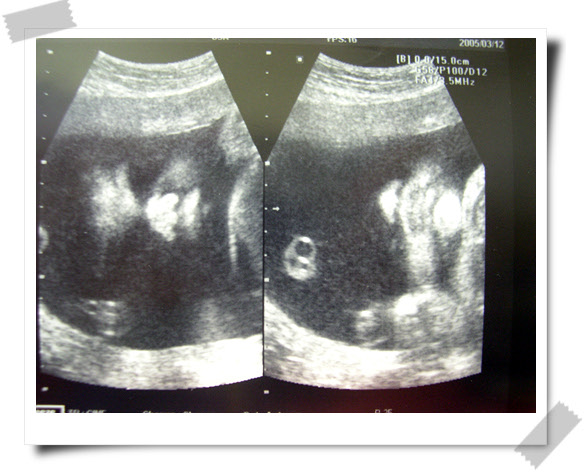

30주+2일 (2005년 3월 12일 토요일 아가야~)

<b><center>또렷하게 보이는 코랑...입</b></center>

병원 옮기고 처음으로 아빠, 시흔이와 함께 둘째를 보러갔다.

예진을 끝내고도 한참을 기다려 보게된 둘째...역시 크댄다... ^^;;

3주내 엄마가 늘어난 몸무게만큼 둘째가 커버렸다.

아마도 시흔이 공주때보다 더 큰 아기가 태어날것 같단다...

* 우리아가 - 2.0kg (1~2주 성장이 빠른 상태..)